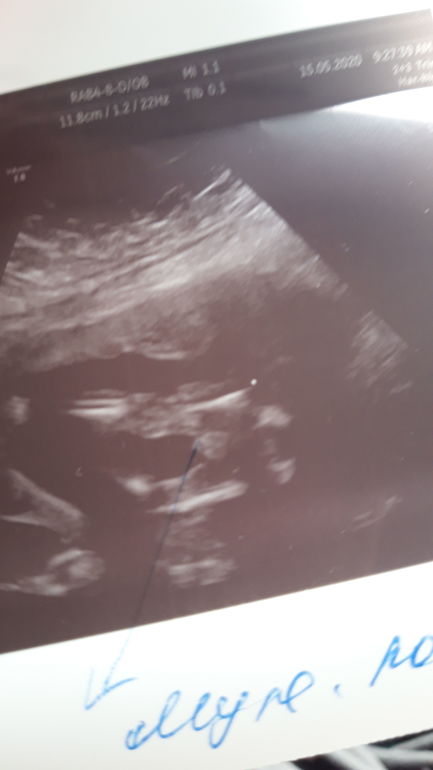

На первом скрининге сказали мальчик,неделю назад говорили девочка,сегодня снова мальчик😁кто же все таки?

На снимке мужское достоинство.